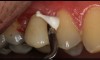

A male patient presented with an unrestored endodontically treated tooth. Because of the retentive qualities of this preparation, a bioceramic cement was considered. When the temporary was removed, there was inflammation in the tissue surrounding the distal margin. In addition, this patient showed significant plaque issues (Figure 4 and Figure 5). This is a difficult situation we all face in dentistry. Any type of resin cement would be prone to long-term failure due to the high likelihood of bacterial contamination, as well as moisture contamination, that could undermine the quality of the bond.

Fig 4. Patient presented with unrestored endodontically treated tooth.

Figure 4

Fig 5. Occlusal view of unrestored premolar.

Figure 5